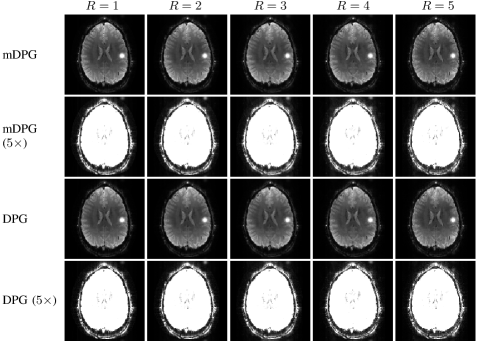

Figure 7 shows reconstruction results from the second set of in vivo diffusion EPI brain acquisitions (with different acceleration factors), with zoom-ins shown in Supporting Information Fig. S9 for improved visibility. Consistent with the results shown for the gradient-echo EPI data in Fig. 1, we observe that all methods perform well for low acceleration factors. As the acceleration factor increases, the performance of each method degrades, with RAC-LORAKS showing a lower qualitative degradation in comparison to the other methods at the very high acceleration factors . Note that at high acceleration factors (e.g., ) the reconstruction quality for RAC-LORAKS is not quite as good as for the gradient-echo EPI dataset shown in Fig. 1. We believe that this should be expected, since as mentioned before, diffusion EPI data can be considered more challenging than the gradient-echo EPI data due to SNR issues, eddy current effects, motion-induced phase effects, and contrast mismatches between the ACS and EPI datasets.

Figure 7: ACS data and reconstruction results for in vivo diffusion EPI brain data for different parallel imaging acceleration factors. For improved visualization, zoomed-in versions of these results (corresponding to the spatial region marked with a yellow rectangle in the first column and first row) are shown in Supporting Information Fig. S9. It should be noted that the subject appears to have slightly moved between scans, so that there is not perfect correspondence between anatomical image features across different acceleration factors.